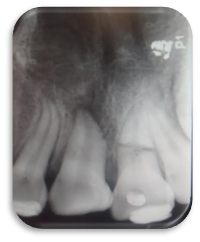

Se apreció lesión apical en la pieza 2.1 (imagen 1). Al realizar el acceso con una fresa bola de tallo largo #6 se tomó la radiografía de cavometría con la lima Flex R #20 a 20 mm (imagen 2), posteriormente se colocó pasta de hidróxido de calcio y se dejó durante un mes, después se tomó la radiografía de cronometría con cono #55. Se realizó la técnica de Crown Down para limpiar la parte coronal. Se instrumentó a partir de la lima #20 hasta la lima #55 master a 20 mm y se realizó retroceso hasta la lima #80. Al término del tratamiento se usó la técnica de condensación lateral combinada con vertical de gutapercha (imagen 3).

Imagen 1

Imagen 2

Imagen 3

Imagen 4